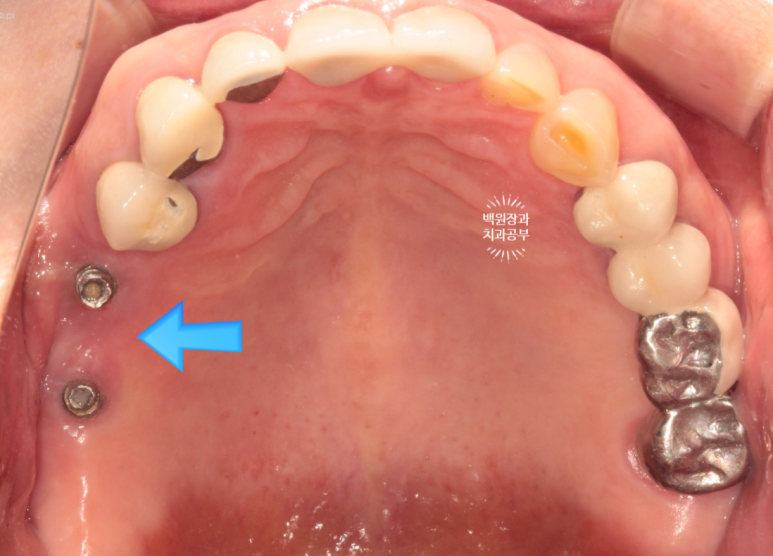

70대 중반 남자 환자분이셨습니다.

위턱에 네개의 임플란트를 이용한 임플란트틀니를 5년 동안 사용하고 계셨는데, 계속 고름이 나오신다는거에요...

노란 점선이 보이시나요? 잇몸뼈의 높이입니다.

상당한 양의 임플란트 주변 뼈가 녹아서 없어져 버린것을 보실 수 있어요.

환자분은 임플란트를 엄청 빼고싶어 하셨습니다.

저희 치과 잘 찾아오셨습니다....!

금색의 locator가 장착된 임플란트의 주변에 고름이 맺혀있는게 보이시나요..?

네개의 임플란트 모두 상당한 임플란트주위염에 시달리고 있는 것을 볼 수 있었습니다.